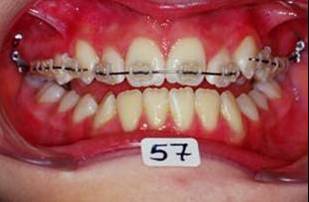

En fouillant dans mes cas j'ai trouve celui ci qui presente une beance assez importante. Je me suis rappele qu'un certain message etait lance il y a qq temps a propos d'un enfant qui presente une beance et de savoire comment faire dans ce cas. Je pense qu'il est interessant de voir comment les uns et les autres prennent en charge ce type de cas. Il s'agit d'un fille de 12 ans, succion de pouce, interposition linguale totale, beance de molaire a molaire, respiration mixte, incompetence labiale au repos, fonction labiale serree. Le total quoi!!! Voici la premiere serie de photos

la suite de documents, comme vous allez le voir le premier moyen est un qh, mais quelle sera la suite?

1- RDV 1: QH

2- RDV 2 : Commencer avec ecran buccal + exercice de respiration

3- Quant elle est capable de garder oral screen toute la nuit je considere que la batail est gagnee

4- Collage de l'arcade sup, presque 6 mois apres et voici le photo apres seance de college